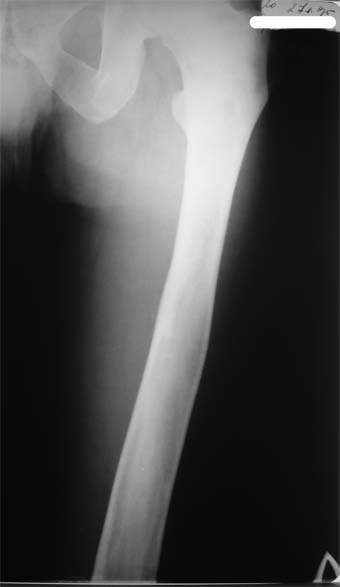

Коллеги!Пациент Д., 35 лет, В 1985 году был поставлен диагноз гемигипоплазия правой нижней конечности. Укорочение 5 см, в 1987 году остеотомия правого бедра, аппарат 4 месяца, удлинили на 2 см из-за нагноения спиц аппарат сняли. В настоящее время Жалобы на дискомфорт, тяжесть в левом бедре, голени при длительной ходьбе, при длительном лежании на левом бедре. Эти жалобы беспокоят втечение 5-6 лет. В 1999 году выявили "изменения" (со слов больного, выписки нет на руках) бедренной кости и костей голени слева. Тогда же предложили в ЦИТО срочно делать какую-то операцию. При осмотре: Правая нижняя конечность. Имеются рубцы на правом бедре по наружной и внутренней поверхностям. Ограничения движений в коленном суставе нет. Кровоснабжение, иннервация сохранены. Левая нижняя конечность. Левое бедро увеличено в объеме, при пальпации пальпируется бедренная кость большего диаметра по сравнению с левым бедром. Пальпация безболезненна. Голень обычной формы. Объем движений в суставах полный. Кровоснабжение, иннервация сохранены. Имеется разница в длине конечностей правая короче на 4-5 см за счет бедра и голени. В приложении вид больного и рентгенограммы бедра 2001 год и 2005 год. Что бы это могло быть? О чем можно думать? Онкология? С уважением Коробушкин Глеб Владимирович Российский государственный медицинский университет кафедра травматологии, ортопедии и ВПХ, доцент

Остеосклеротическая стадия болезни Педжета. Имею двух подобных больных по 15 -20 лет наблюдения. В острой стадии - текли как классическая саркома. "За" - все (рентген+биопсия+клиника) - отправили хоронить, а в результате живы и имеют рентген-картинку похожую Вашей. Поройтесь в минеральном обмене и в почках. Удлинять подобные кости опасно. Можно -биопсию на всякий случай (из зоны склероза и зоны пороза).

В настоящее время имеется умеренный рубцовый процесс правого бедра не мешающий на объем движений в суставах. В коленном суставе слева бедро обычное, голень - булавовидное утолщение проксимального конца большеберцовой кости. На рентгенограммах тотальное поражение кости с увлечением в процесс проксимального эпиметафиза, поражение характерно для болезни Campanatsehi

У больного полиоссальноая форма фиброзной дисплазии с поражение левой бедренной и большеберцовой кости. На рентгенограммах - тотальное разрастание и остончение кортикального слоя. Имеется удлинение левой нижней конечности на 2,5-3 см за счет голени. Больному показано оперативное лечение левой большеберцовой кости.